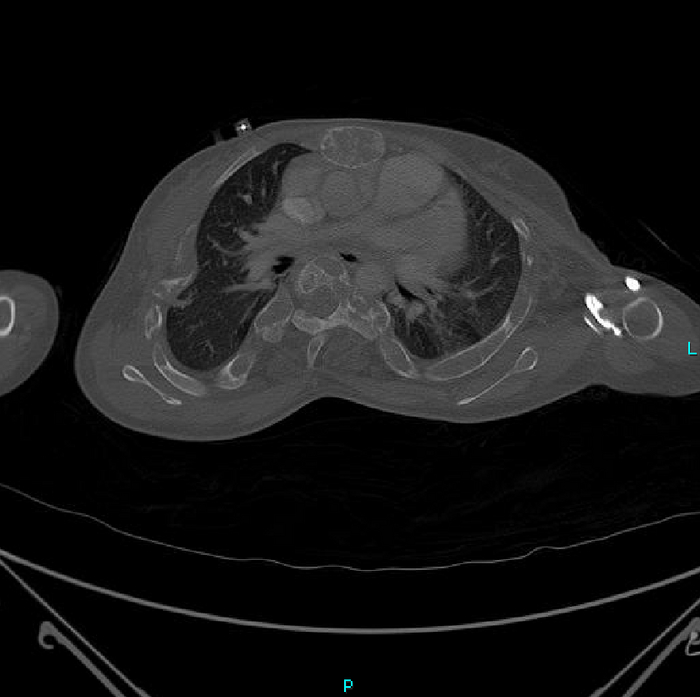

Но вернёмся к случаю: Пациент - девочка, 15 лет. Поступила после ДТП. У нас было проведено КТ-обследование по протоколу политравмы (голова / шея / грудь / живот / таз), где свежих переломов обнаружено не было, но были непонятные леденцы с костями, а именно структура и форма костей со следами старых переломов (грудная клетка и таз с бедренными костями) и, как следствие, их деформацией + следы проведённого остеосинтеза (операция с последующей фиксацией кости тем или иным способом) обоих бедренных костей. Сегодня без пометок / стрелочек, так как картинки говорят сами за себя (всё в костном окне, и всё, что мы видим - кости):

Структура костей напоминала таковую при фиброзной дисплазии (аномалия развития костной ткани с замещением нормальной кости фиброзной тканью, не является опухолью), но, обычно, эти диcплазии возникают в одном месте, т.е. поражают 1 кость (моностотическая форма) и, намного реже, бывают множественные поражения (полистотическая форма), но не всего скелета, как в нашем случае.